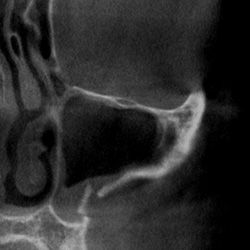

Funktionsdiagnostik und -therapie

• Ausschluss primärer Kiefergelenkerkrankungen

• Erfassung differential-therapeutischer Befunde

• Knöcherne Erkrankungen des Kiefergelenks